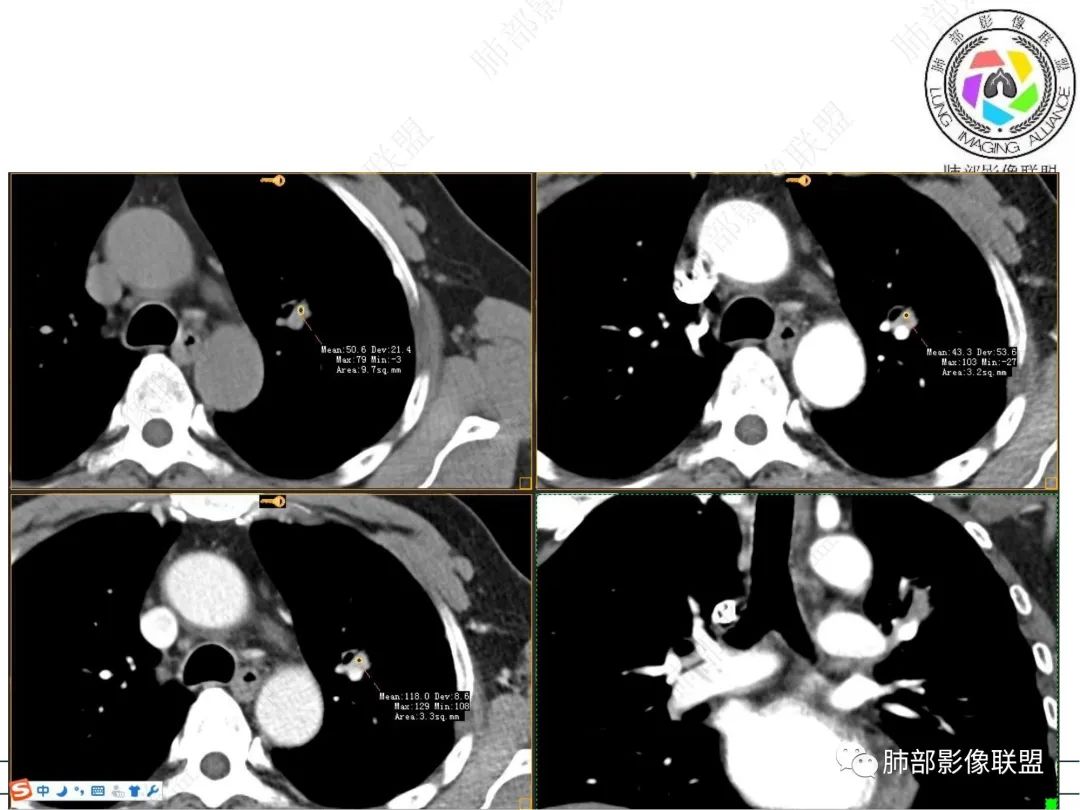

实性部分强化明显,边缘平直

1、临床:57岁男性,3年逐步增大。孤立病灶持续三年原地坐大,符合肿瘤性病变,恶性程度不高或者早期进展缓慢。良性肿瘤常多年静止或进展极其缓慢。炎性病灶“星火”可以燎原,临床表现也会逐步加重。尽管继发性肺结核可以相对惰性,但病灶强化不明显,多结节、多卫星、多新旧不等,相对清楚硬朗。

2、病灶以实性密度为主,前、外侧蔓延,GGO部分边界清楚,部分欠清

支气管未见受明显侵犯,未见阻塞,壁增厚,狭窄或扩张。

软组织+重建;病灶实性部分不是类圆形,密度相对均匀柔和。

肺门区病灶与支气管关系不密切,强化显著、磨玻璃晕等等容易想到的是肺腺癌。而不首先考虑与支气管密切相关恶性肿瘤,如鳞癌、类癌、粘液表皮样癌等等。

1、良性肿瘤——PSP,符合点实性部分强化明显,伴出血,周围长期GGO。不符合点:占位效应不够,对附近支气管无明显推移,整体形态非类圆形。生长太快。此外病灶的GGO,在前外,内侧没有,应该周围都有,不符合。

2、特殊炎症:隐球菌,支持点结节,逐步增大,周围晕,边缘稍收缩;不支持点:位置偏内侧,支气管与其无关;病灶存续时间太过漫长,未形成群落。